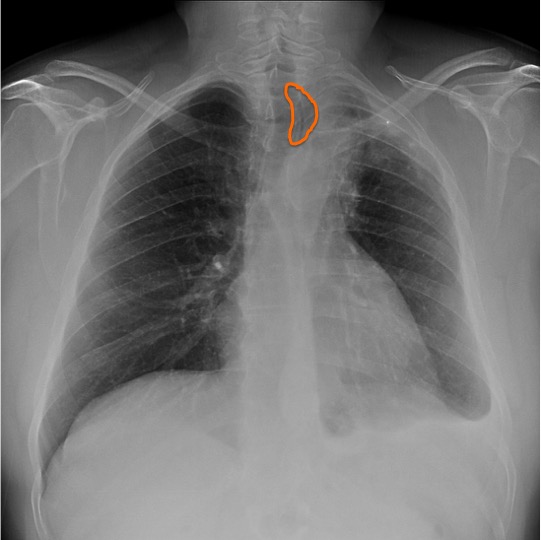

CASO: Fumador a control.

Hallazgos:

- Paciente con signos de EPOC tipo enfisema y tractos fibrosos: fibroenfisema.

- Cisura de la acigos como variante de la normalidad.

- Adenopatía calcificada en hilio izquierdo.

CISURA DEL LÓBULO DE LA VENA ÁCIGOS:

Indica una variante de la normalidad. El lóbulo de la vena ácigos se crea cuan un vena ácigos desplazada hace un fisura profunda en el pulmón. En la placa simple se ve como una línea fina que cruza el ápex del LSD.